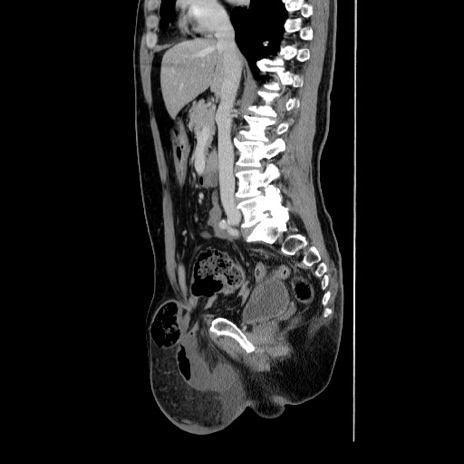

症例34(矢状断像)

【症例】60歳代 男性

【主訴】右鼠径部膨隆

【現病歴】1年程前より右鼠径部膨隆あり。自己にて還納可能だったため放置していた。3時間前より右鼠径部の脱出を認め、還納困難となり受診。

【既往歴】高血圧

【身体所見】右鼠径部に小児頭大の膨隆あり。弾性硬であり、用手還納は困難。左鼠径部にも膨隆を認める。脱出はなし。

【データ】WBC 15500、CRP 測定なし